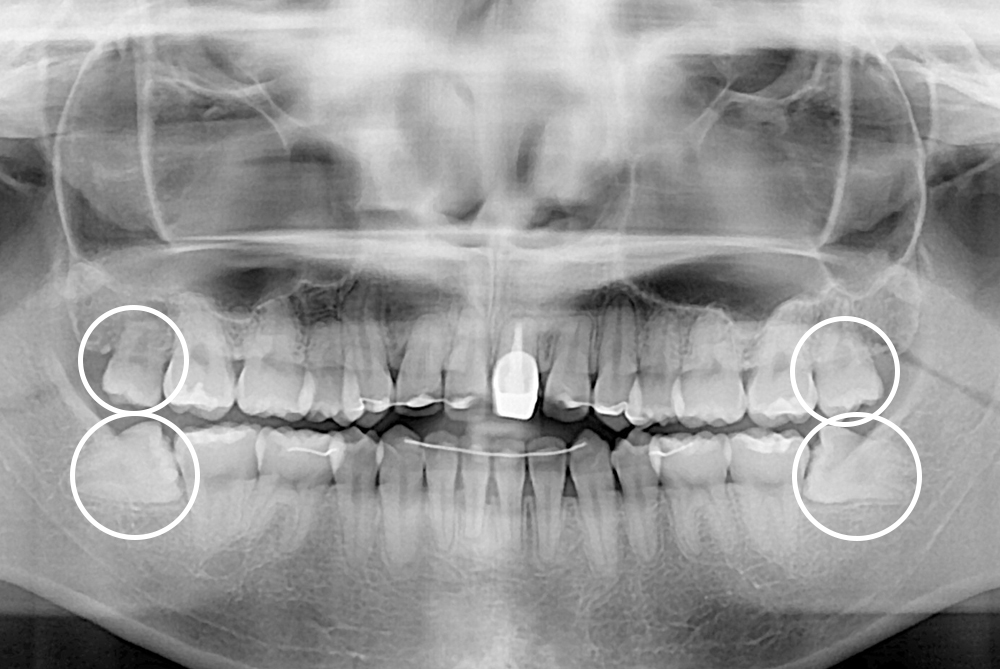

[사랑니] 매복 사랑니 발치

치료후 : 2021-10-21

세종치과는 구강악안면외과학 박사이신 원장님이 발치하는 치과입니다.